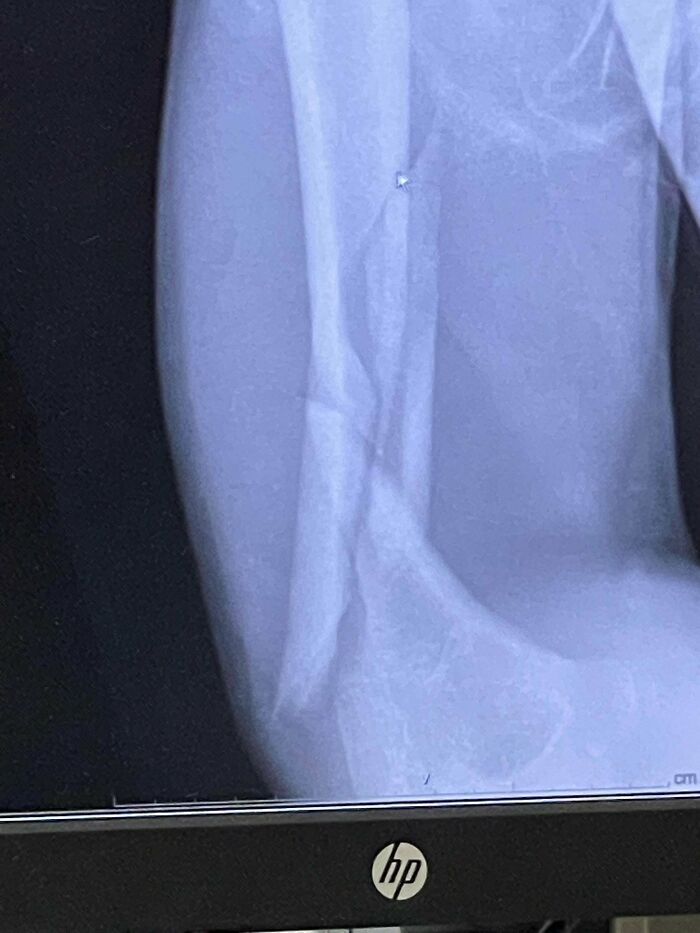

Me rompí y me disloqué el brazo. Feliz cumpleaños a mí